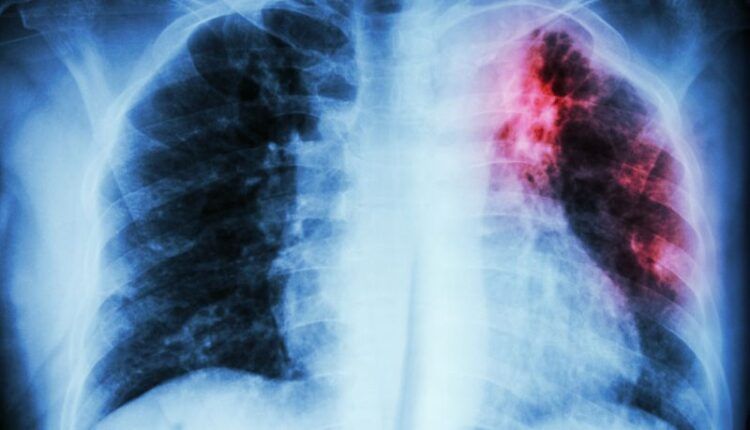

La pandemia de COVID-19 ha anulado años de progreso mundial en la lucha contra la tuberculosis, una enfermedad causada por un germen que suele afectar a los pulmones.